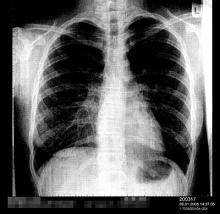

Lungenentzündung (hier ein Röntgenfoto

einer einseitigen Lungenentzündung) wird durch

Quecksilbervergiftung durch Quecksilberdampf

begünstigt |